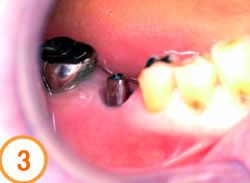

抜歯後すぐにインプラントを埋入する方法です。腫れも痛みもほとんどありません。抜歯即時埋入法は、条件が揃えばより審美的な結果が得られる術式です。この方法を行うには、骨が十分にあることや抜歯する部位の歯肉があること、口腔衛生状態が良好であることなど即時埋入できるかどうかいくつかの条件があります。手術から1~2月程度で歯が入ります。

抜歯したばかりで大きな穴が開いています

歯肉の治りを待ちインプラントを埋入します

アバットメントを入れたところです

歯が入りました